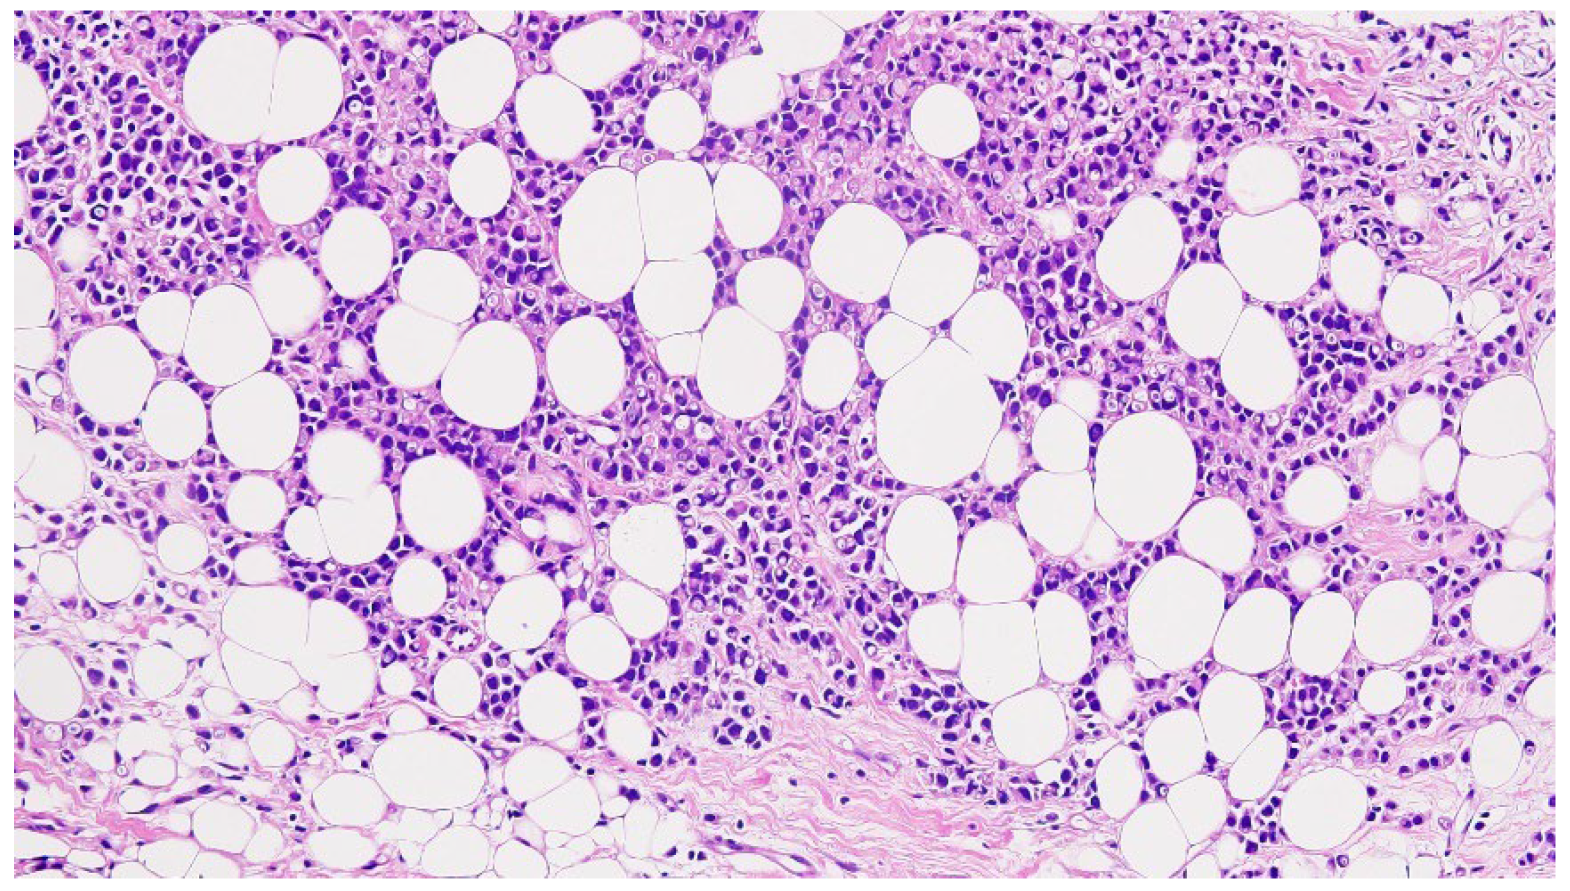

- The diagnosis of invasive ductal carcinoma and its classification as cT3N1M0 and pT3N1M0 for the primary right IMR accessory breast cancer, stage IIIA, and cT2N0M0 of the native right breast cancer;